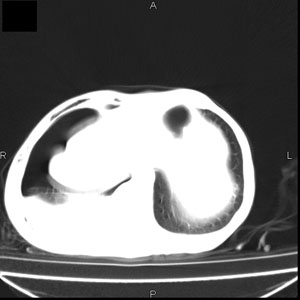

患者男,77岁,于3日前从树上摔下,头部查ct示蛛血,硬膜下出血,上腹部ct未见明显异常,右侧胸腔积液,左侧如常。肺部拍片示右侧肋骨多发骨折住院后今日来查肺部ct,我看到的是1。右侧胸腔血气胸并右肺上叶,中叶压缩性肺不张,2。右肺下叶肺挫伤并多发肋骨骨折,肌内及皮下积气3。左侧少量胸腔积液,我想请教的是3天前左侧胸腔里没有积液今天怎么出现了呢,是什么原因呢?请讨论。

支持楼主诊断。液体来源:1、血液成分,外伤所致。2、胸膜腔渗液—由于肺压缩、活动度下降,肯定胸膜吸收有问题,导致积液增多。

1、外伤出血需要一定的时间

2、气胸存在时间长了,产生的胸膜渗液